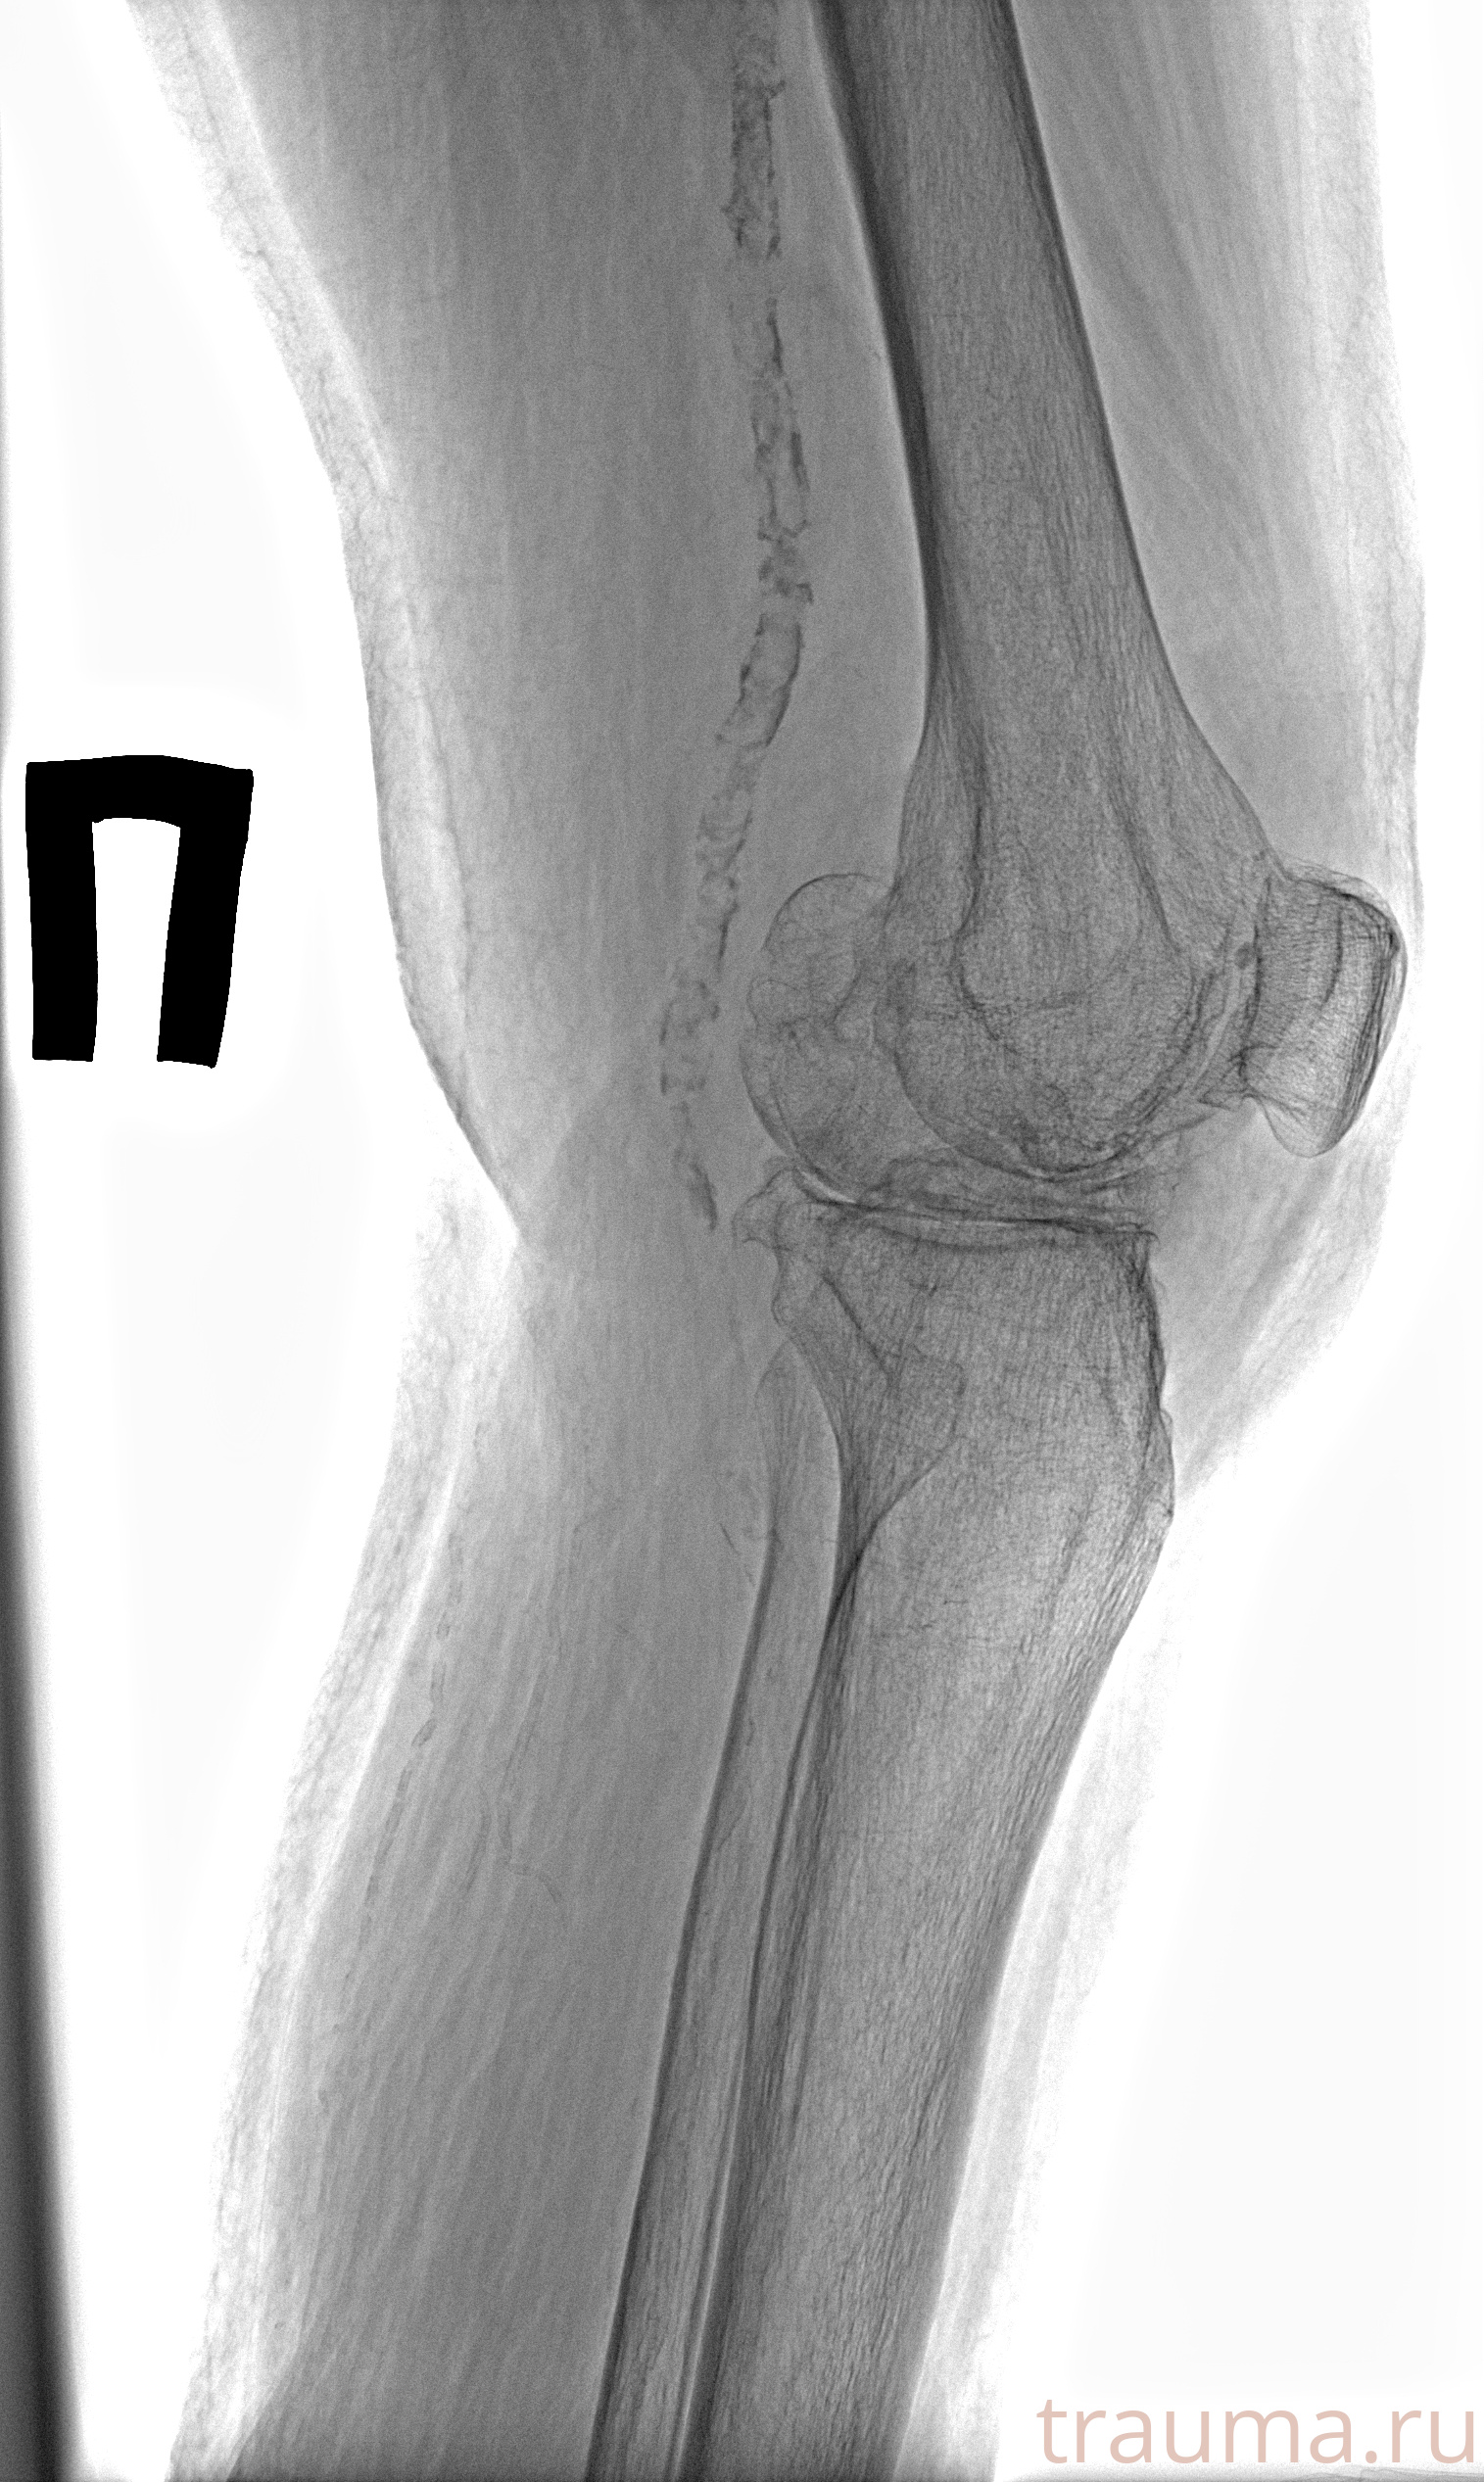

Рентген на дому: по вашему адресу приезжает врач-рентгенолог, травматолог-ортопед с мобильным рентгеновским аппаратом, проводит диагностику травмы или заболевания, делает необходимые рентгенограммы, дает рекомендации по дальнейшему лечению. Получить качественные снимки в домашних условиях возможно благодаря уникальной методике, разработанной МосРентген Центром для института  Склифосовского